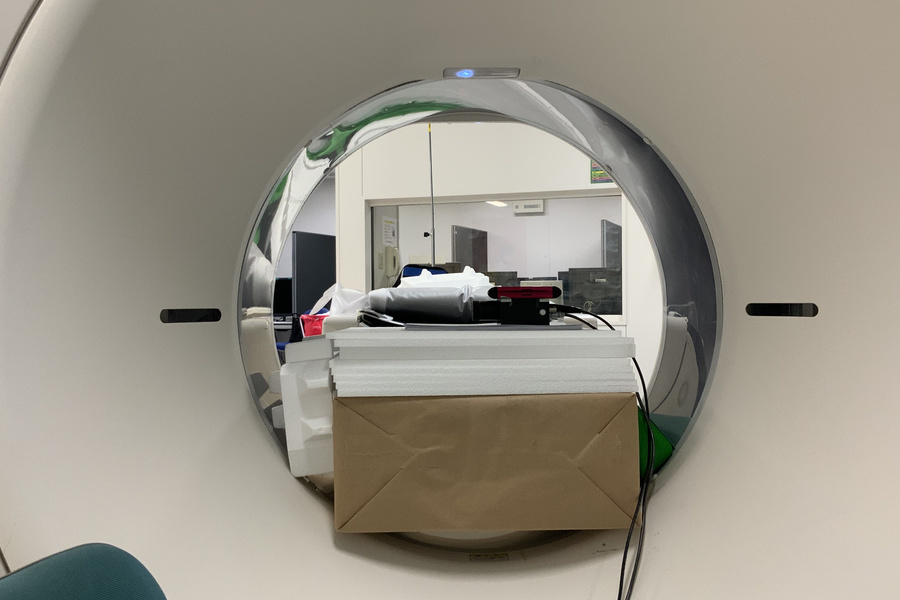

CT検査の散乱線測定 (2024/4/25)

- 施設:藤田医科大学病院 モダリティ:CT 測定器:Accu Gold, 1800cc電離箱

実験者:西原、戸田、伊藤、大坪、石田、高木、山下、村松

実験系:Aquilion ONE のガントリ側方における散乱線の入射方向について測定を行いました

CT検査の散乱線測定 (2024/4/24)

実験者:西原、戸田、伊藤、高木、山下、細野

CT検査の散乱線測定 (2024/4/18)

CT検査の散乱線測定 (2024/4/17)

実験者:西原、戸田、伊藤、細野、荒木

CT検査の散乱線測定 (2024/4/16)

実験者:西原、戸田、伊藤、石田、細野、荒木